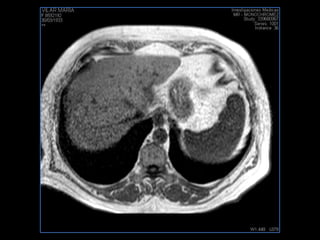

PROTOCOLO hígado graso AXIAL in phase y out phase AX T1 y AX fat sat +SAG T2  CON   GADOLINIO :  COR T1+AX T1(DIN) SAT: NO  FASE: RL THK: 4MM  COIL:  GAP: (FACTOR 1.4)  FOV: 40 CM NEX:2 SINCRONIZACION RESPIRATORIA EN 3 O 4 CICLOS ALE

PROTOCOLO hemocromatosis AXIAL supresión grasa /AX multieco en higado COR T2 AX T1 +SAG T2  CON   GADOLINIO :  COR T1+AX T1 SAT: NO  FASE: RL THK: 4MM  COIL:  GAP: (FACTOR 1.4) 1MM FOV: 40 CM NEX:2 SINCRONIZACION RESPIRATORIA EN 3 O 4 CICLOS ALE